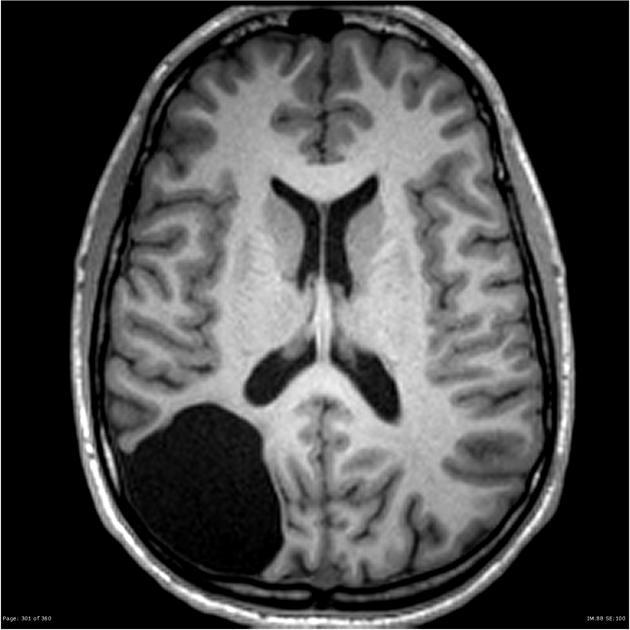

一名9歲女童今年初起突發癲癇症狀,甚至一個月內癲癇二度發作,先是左手疼痛而後全身抽蓄,嚇壞眾人。他院醫生為女童照電腦掃描卻一直找不出原因,直到近期再度癲癇發作,被轉送至羅東博愛醫院急症室治療,檢查後赫然發現大腦出現異常空腔及腦脊髓液淤積。

此案經羅東博愛醫院兒童神經專科段必純醫生安排磁力共振與腦電波仔細檢查,並會診神經外科黃安平醫生,兩人判斷是因右側額葉水囊造成腦部不正常放電,才導致癲癇發作,必須安排開顱手術治療。

在電腦導航系統3D成像的輔助下,黃安平醫生得以平穩且精準執刀。開顱後伸入顯微器械,避開血管,將病灶水囊做出開口,將水囊與蜘蛛網膜下腔打通,讓水分流通進出,清除積水、釋放腦壓。傷口隱藏在髮線內,以最微幅的傷害成功完成這一例高難度腦部手術。